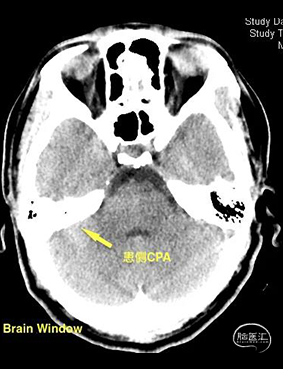

头颅CT(2021-09-14),术前阅片,手术预判。